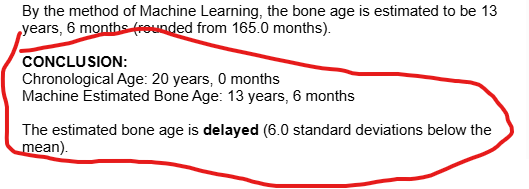

these AI's told me my bone age looks like 18 and 13. YES THIS BONE AGE AI WEBSITE SAID MY BIOLOGICAL AGE LOOKS 13 ACCORDING TO THE XRAY.

these AI's told me my bone age looks like 18 and 13. YES THIS BONE AGE AI WEBSITE SAID MY BIOLOGICAL AGE LOOKS 13 ACCORDING TO THE XRAY.